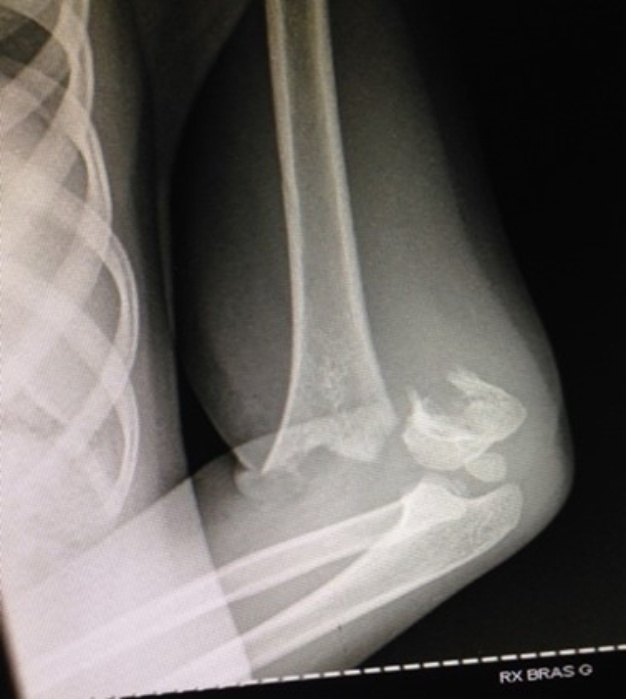

In 54.7% of cases, surgical intervention involved open reduction through a posterior approach and cross pinning (as seen in Figure 2). This finding aligns with the results reported by Fernandez et al. [18]. Due to the absence of a fluoroscope, the open reduction is visually assessed, followed by X pinning. Post-pinning, no elbow immobilization is applied in our patients.

Figure 2. Radiological images depicting a type III FSCH as classified by Gartland in an 8-year-old patient who underwent surgical treatment involving X pinning (Department of Pediatric Surgery, CHU ME).